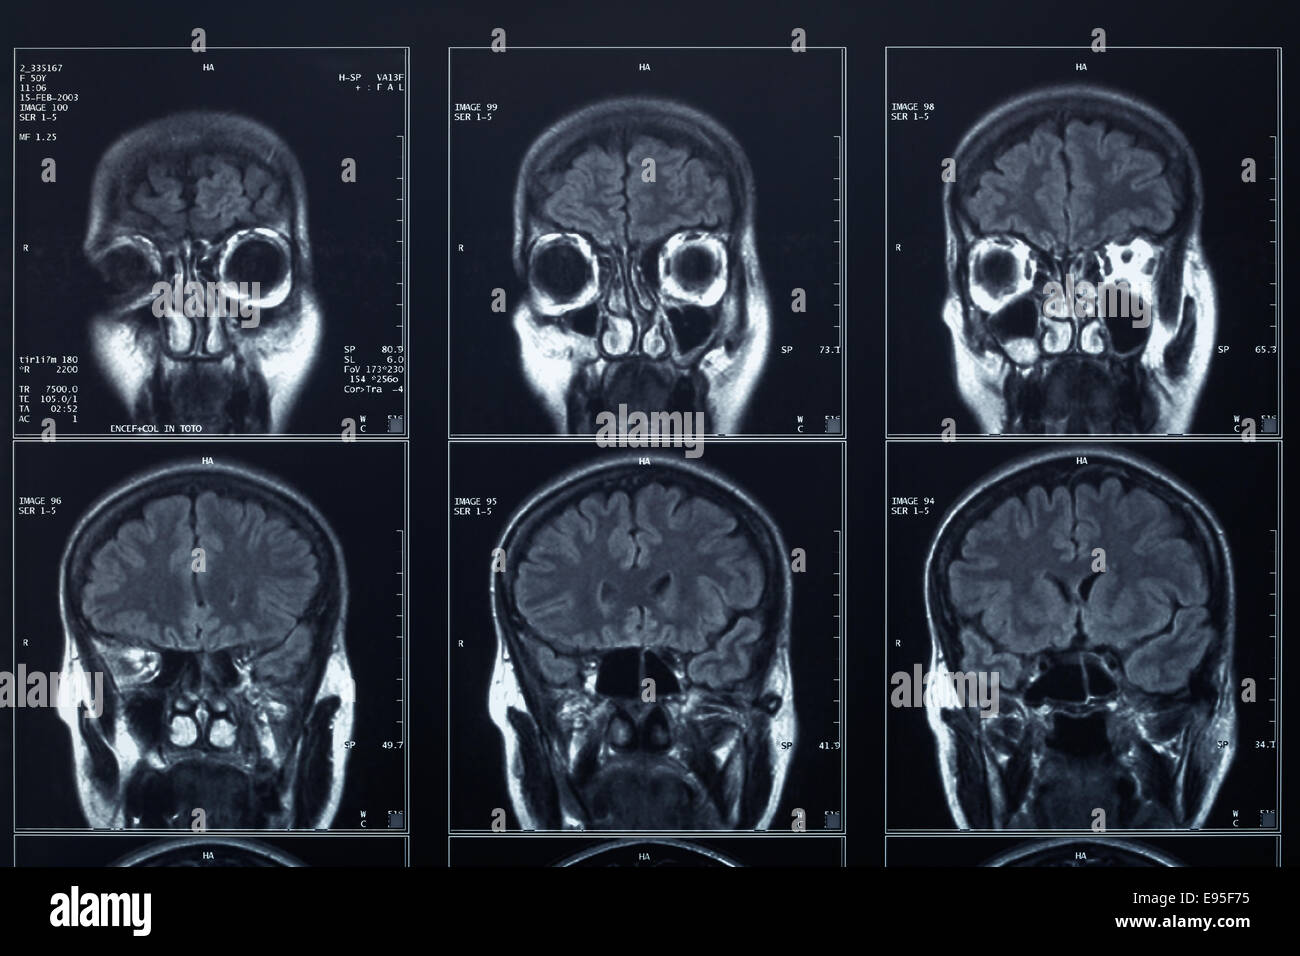

L Imaging Dell Encefalo Tc Ed Rm A Confronto

Risonanza Magnetica Encefalo Medical Imaging Caserta

Tecniche Di Diagnostica Per Immagini In Neurologia

Risonanza Magnetica Encefalo A Cosa Serve Radiologia Italia

Atlante Di Resonanza Magnetica Del Cervello